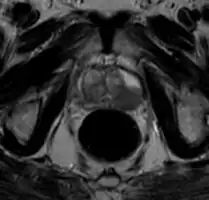

Ultrasound and magnetic resonance imaging (MRI) are the two main imaging methods used for prostate cancer detection.

-

MRI Organ-confined prostate cancer -

MRI

On MRI, the central and transitional zones both have lower T2 signal than the peripheral zone. Since the central and transitional zones cannot be distinguished from each other, they can be best described as the central gland on MRI. Thus, the peripheral gland has a higher signal on T2WI than the central gland. In the peripheral gland, prostate cancer appears as a low-intensity lesion. However, in the central gland, low-intensity lesions cannot be distinguished from the low-intensity central gland. Diffusion restriction is instrumental in identifying and characterizing central gland lesions. Lymphadenopathy can be seen best on postcontrast, fat-suppressed T1WI.

Other regions can be described on MRI. The anterior fibromuscular stroma and the prostate capsule along the posterior and lateral prostate have a low T2WI signal, in contrast with the bright signal of the peripheral zone. Extraprostatic extension can be seen with disruption of capsule integrity.

As of 2011, MRI was used to identify targets for prostate biopsy using fusion MRI with ultrasound (US) or MRI-guidance alone. One study reported that given a clinical suspicion, MRI-guided fusion biopsy detected clinically significant cancer in 38% compared to 26% in the standard biopsy group.[75] In candidates for active surveillance, fusion MR/US-guided prostate biopsy detected 33% of cancers compared to 7% with standard ultrasound-guided biopsy.[76]

The prostate imaging-reporting and data system defines standards of clinical service for multiparametric MRI (mpMRI), including image creation and reporting. PI-RADS version 2 scoring has shown a specificity and sensitivity of 73% and 95%, respectively, for detection of prostate cancer.[77]

Prostate MRI is also used for surgical planning for robotic prostatectomy. It helps surgeons decide whether to resect or spare the neurovascular bundle, determine return to urinary continence, and help assess surgical difficulty.[78] MRI can also be used to target areas for research sampling in biobanking.[79][80]